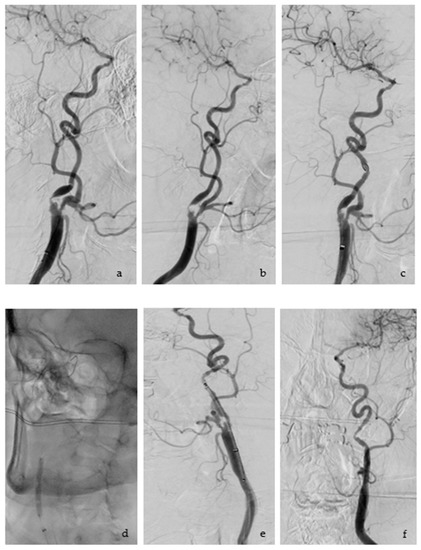

The technical success rate for this study was 100%. Figure 6 shows the steps of the CAS Procedure.

Figure 6.

CAS Procedure: (a) showing the anterior-posterior view of the stenosis of the ICA; (b) lateral projection of the stenosis; (c) the stenosis has been crossed with the filter system, this can be recognized as a round radiopaque object above the stenosis; (d) carotid angioplasty; (e) post angioplasty, stent positioning and measurement before final implantation; (f) angiography control after stent has been deployed.